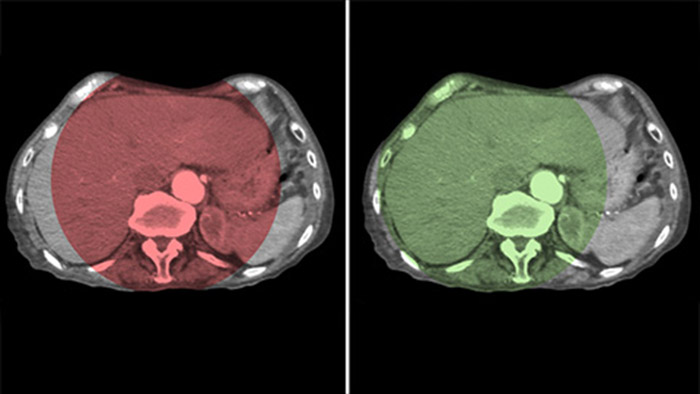

Fusión de imágenes con Dual View

Dual View permite la visualización simultánea de dos conjuntos de datos de la THC. Tanto la fase arterial como la retrasada se pueden mostrar una al lado de la otra o en una sola vista de superposición fusionada.